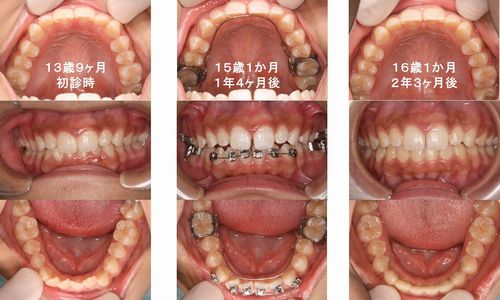

13歳の女子中学生、過蓋咬合(咬み合わせが深いために下の前歯が見えない)で下顎前歯部叢生(ガタガタ)の症例です。上下に3Dリンガルアーチを装着して咬み合わせを浅くしていきました。1年4ヶ月後に下あごにメタルブラケットをつけて叢生の改善を開始しました。上あごは、歯並びが整っていたのでそのまま3Dリンガルアーチで保持しています。更に11ヶ月経過して上下の歯並びが整ったので装置を外しました。下あごは前歯の裏側を細いワイヤーで固定して後戻りを防いでいます。

治療費:¥568,000(税別) 治療期間:2年3ヶ月